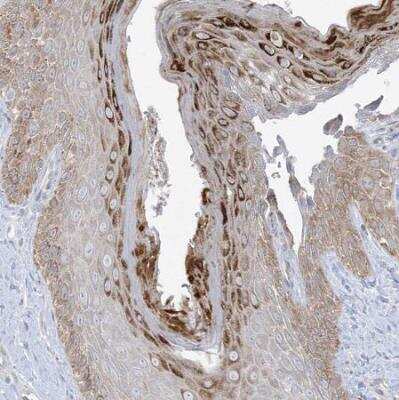

Immunohistochemistry-Paraffin: CD2F-10/SLAMF9 Antibody [NBP1-84593] - Staining of human skin shows moderate membranous and cytoplasmic positivity in squamous epithelial cells.